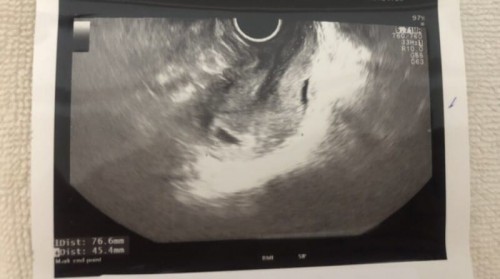

มีประจำเดือนวันแรกครั้งสุดท้าย 18 ม.ค. ตรวจเจอ 2 ขีดครั้งแรก 18 ก.พ. ไปหาหมอวันที่ 20 มี.ค. หมออัลตราซาวด์เจอถุงตั้งครรภ์ในมดลูกแต่มีขนาดเล็ก คำนวณจากเครื่องอัลตร้าซาวน์ได้ 4 สัปดาห์เองค่ะ อัลตราซาวด์ทั้งหน้าท้องและผ่านช่องคลอดเลยค่ะ หมอนัดอีก 3 สัปดาห์มาลุ้นกันต่อว่าจะท้องลมรึป่าว ✌🏻✌🏻